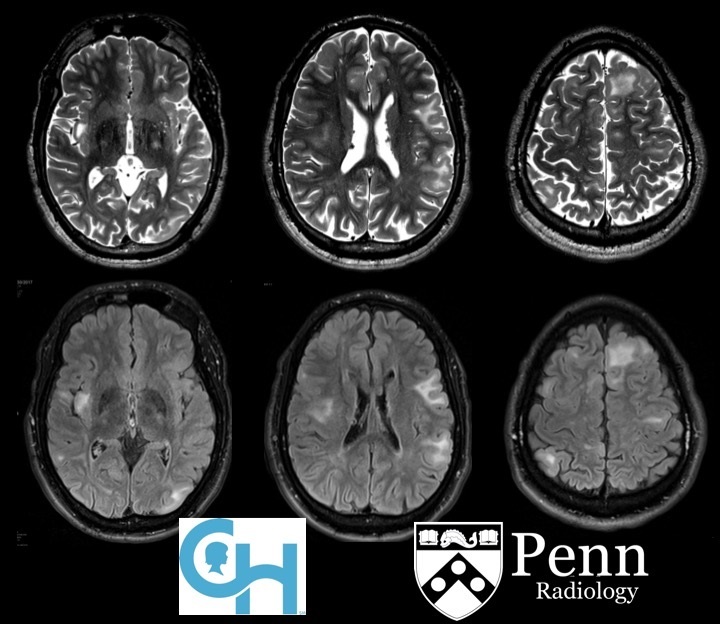

Hypoxic-ischaemic injury to gray matter (thalami and lentiform nuclei) demonstrates characteristic T1 hyperintensity and T2 hypointensity

Neonatal hypoxic-ischaemic encephalopathy (HIE) is the result of a global hypoxic-ischaemic brain injury in a term neonate, usually after asphyxia.

Radiographic features

In term infants blood flow is ventriculofugal and changes are mainly, like in older children, in watershed-border zones; namely, parasagittal grey matter and subcortical white matter. Profound HIE in term babies results in thalamic and basal ganglia as well as sensorimotor cortex (perirolandic region) injury.

MRI

MRI is the most sensitive and specific imaging technique for examining infants with suspected hypoxic-ischaemic brain injury. Conventional sequences can help exclude other causes of encephalopathy such as haemorrhage, cerebral infarction, neoplasms, or congenital malformations.

A number of patterns of injury are encountered (see patterns of neonatal hypoxic-ischaemic brain injury) depending on the stage of brain maturation and severity of asphyxia, with the following expected signal intensity changes:

T1

grey matter: hyperintense

white matter: hypointense

T2

grey matter: variable depending on the time of imaging and presence of haemorrhage

white matter: hyperintense

DWI/ADC

diffusion restriction first week

ADC pseudonormalisation occurs at the end of the first week